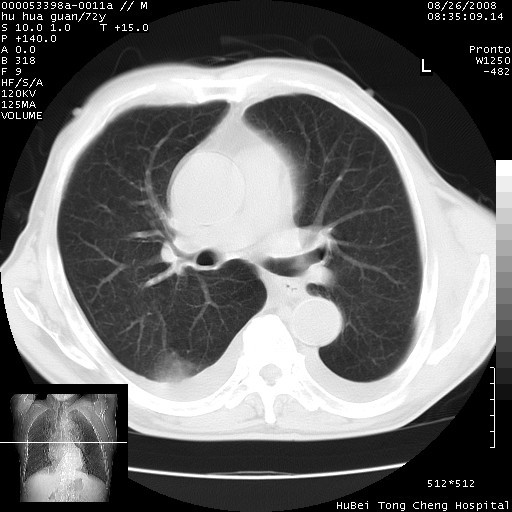

标题: CT15582:M,72Y。请老师帮分析胸部病变。

可以明确的说。肯定不是主动脉夹层破裂出血!考虑为淋巴瘤或间叶组织来源的恶性肿瘤可能性大。右肺小结节建议薄层观察,如能发现恶性征象,那椎前改变就考虑为转移所致。至于双侧少量胸水乃静脉血回流受阻所致。

1、右上肺结节病变,肺泡癌不除外,请随诊;左下肺近后纵隔病变,考虑纵隔型肺癌侵犯大血管可能;

2、右下肺背段少许炎症,双侧胸腔积液,右下肺纤维索条。

降主动脉前移位,后纵隔占位

后纵隔占位,降主动脉前移位;双侧胸腔积液;应排外食管病变侵犯血管可能;